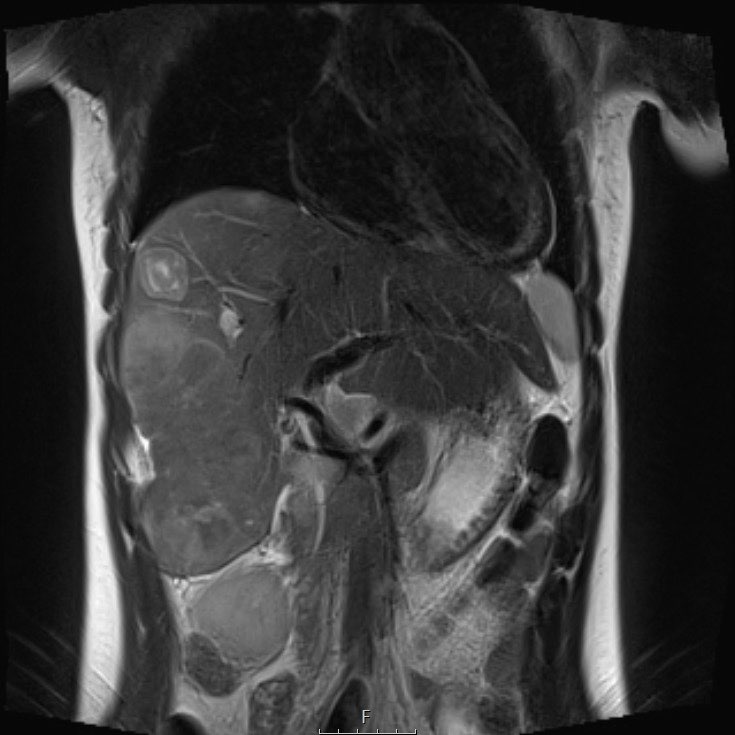

Ví dụ 1

Một bé trai hai tuổi đến khám với triệu chứng sưng vùng bụng.

Trên siêu âm thấy một khối u đặc lớn ở vùng bụng trên. Có một số vôi hóa. Khối u có thể xuất phát từ gan. Khối u trượt trên thận phải.

Tiếp tục với MRI.

MRI shows a solid hepatic mass with multiple small cysts.

Sau khi tiêm thuốc cản quang, khối u được thấy giới hạn ở phân thùy sau và trước phải, được phân định bởi tĩnh mạch gan giữa (mũi tên).

The mass has moderate diffusion restriction.

Biopsy was compatible with an epithelial hepatoblastoma.